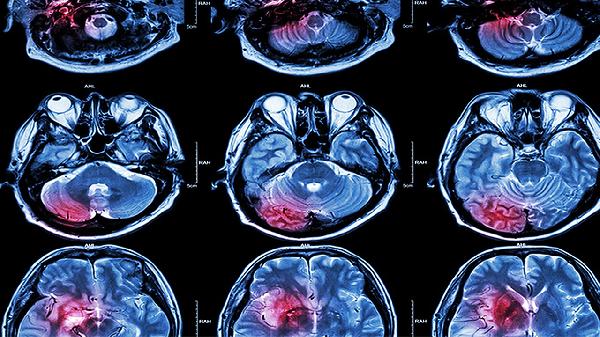

脑溢血对身体有什么影响!

你是否有过突然头晕目眩、眼前发黑的经历?别小看这些信号,它们可能是身体在拉响预警。脑溢血这个潜伏的健康杀手,经常在不经意间给人体带来沉重打击,了解它对身体的影响,就是在为自己的生命多上一道保险。